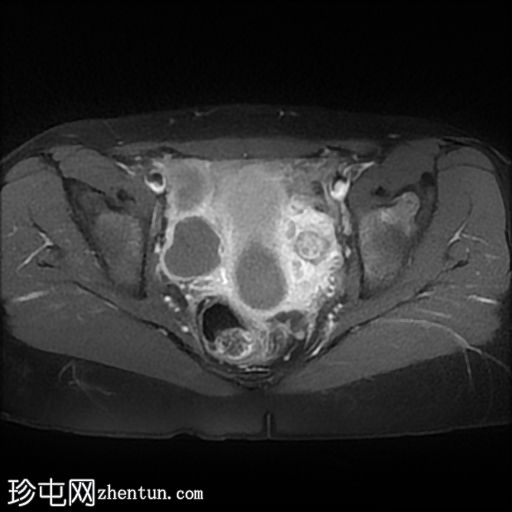

轴向

STIR

子宫体相对较小,发育良好。宫颈发育不全。

阴道整体不显影,远端可见一层细小的纤维组织,在轴向和矢状面T2加权序列上最为明显。

随后,子宫内膜和宫颈腔扩张,出现混合液体/血液降解信号(积血)。它诱发中至高T1信号,伴有依赖性低信号碎片,无病理性强化。

周围轻度盆腔积液,盆腔及附件脂肪平面模糊,信号相似,增强后强化明显。这些发现提示可能有渗漏液/血液积聚,并伴有腹膜反应。

右侧附件卵巢功能性囊肿。